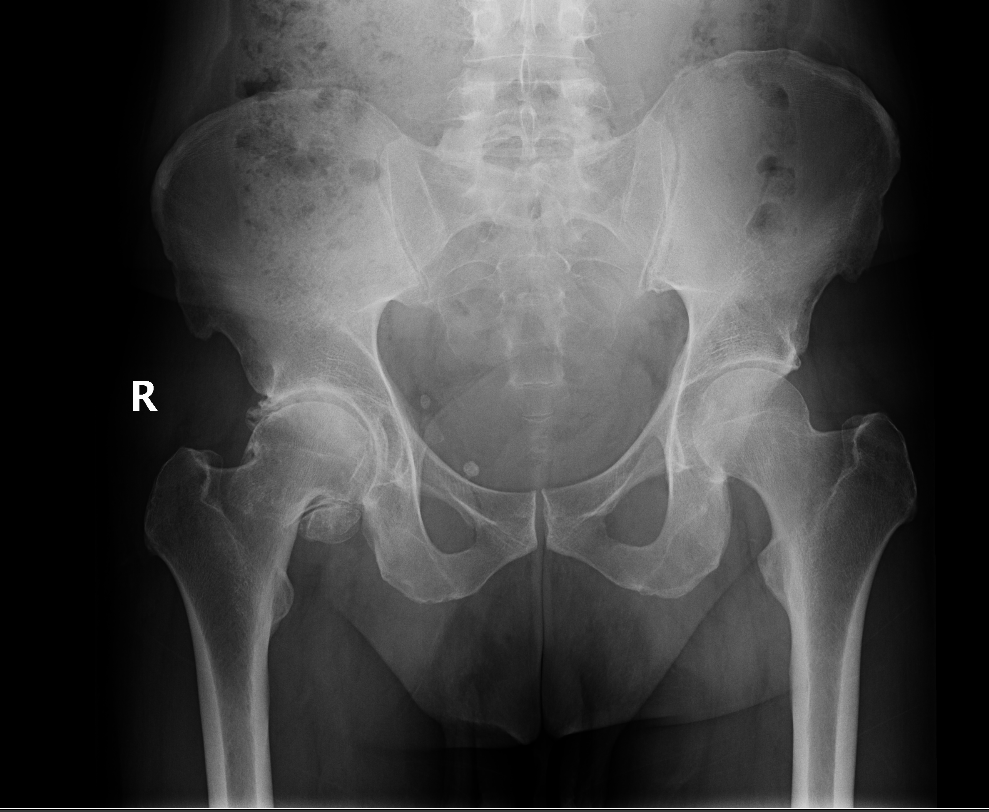

Diagnosis is made by evaluating medical history, physical examination and X-rays.

Arthritis is inflammation of the joints resulting in pain, swelling, stiffness and limited movement. Hip arthritis is a common cause of chronic hip pain and disability. The three most common types of arthritis that affect the hip are:Total hip replacement (THR) is a surgical procedure in which the damaged cartilage and bone is removed from the hip joint and replaced with artificial components. The hip joint is one of the body’s largest weight-bearing joints, located between the thigh bone (femur) and the pelvis (acetabulum). It is a ball and socket joint in which the head of the femur is the ball and the pelvic acetabulum forms the socket. The joint surface is covered by smooth articular cartilage which acts as a cushion and enables smooth movements of the joint.

Arthritis is inflammation of the joints resulting in pain, swelling, stiffness and limited movement. Hip arthritis is a common cause of chronic hip pain and disability. The three most common types of arthritis that affect the hip are:

- Osteoarthritis: It is characterized by progressive wearing away of the cartilage of the joint. As the protective cartilage wears down, the bone ends rub against each other and cause pain in the hip. Rheumatoid arthritis: This is an autoimmune disease in which the tissue lining the joint (synovium) becomes inflamed, resulting in the production of excessive joint fluid (synovial fluid). This leads to loss of cartilage causing pain and stiffness.

- Traumatic arthritis: This is a type of arthritis resulting from a hip injury or fracture. Such injuries can damage the cartilage and cause hip pain and stiffness over a period of time.

The most common symptom of hip arthritis is joint pain and stiffness resulting in limited range of motion. Vigorous activity can increase the pain and stiffness which may cause limping while walking.